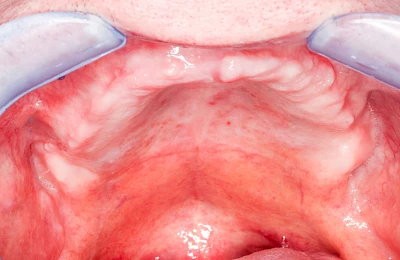

Überbeine im Bereich der Kiefer sind gar nicht so selten. Häufiger im Bereich der Seitenzähne unterhalb des Zahnfleisches, aber auch in der Mitte vom Gaumen. Überbeine haben in dem Sinne keinen Krankheitswert, müssen also nicht operativ entfernt werden, wenn diese nicht stören. Überbeine können ein Anzeichen für Knirschen und Pressen sein.